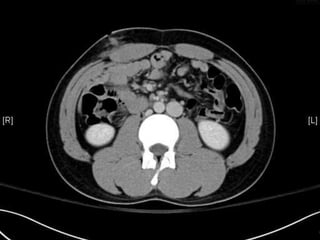

• CT:

 Shanmuganathan(2004)

 Sen:97%, spe:98%, accuracy:98% in penetrating stab wds

 Velmahos(2005)

 GSW: Sen 90.5, Spe: 96%

Radiology 2004:231:775-784

J trauma 2005:59:1155-1161